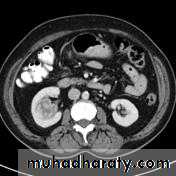

• Heterogeneous necrotic mass on CT scan may extend to the perinephric area, renal vessels with regional LN and distant metastasis to the lungs or bone.